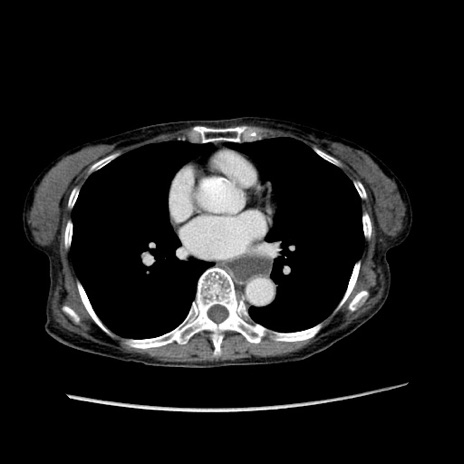

【症例】80歳代女性

【主訴】胸のつかえ感

【現病歴】約9時間前に食後から胸のつかえた感じあり、嘔吐あり、来院。

【既往歴】胃癌(全摘)、胆摘、虫垂炎

【身体所見】心窩部に圧痛あり、反跳痛なし。

【データ】WBC 5700、CRP 0.05